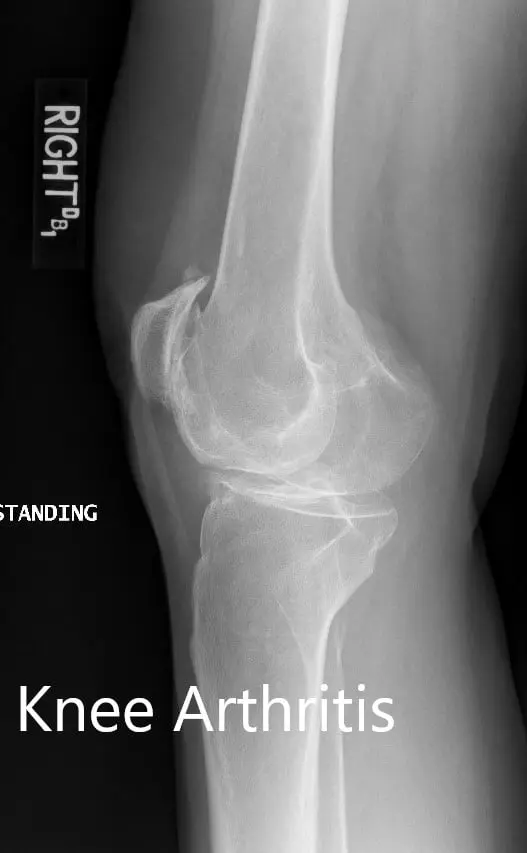

Preoperative X-ray showing the lateral views of the right and the left knee respectively

Preoperative X-ray showing the lateral views of the right and the left knee respectively - img 2

Preoperative X-ray showing the lateral views of the right and the left knee respectivelyComplete Orthopedics patient specific surgical plan for a Bilateral Custom Total Knee Replacement in a 61-year-old male with Knee Arthritis & Genu Valgum Deformity